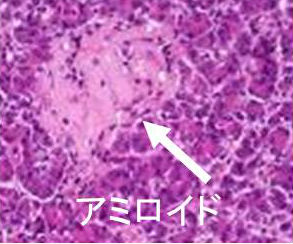

橋本病に合併した結節性甲状腺アミロイドーシスの病理組織標本では、

- アミロイド結節内の甲状腺濾胞構造は破壊され、異物反応や石灰化も存在する(第57回 日本甲状腺学会 P2-061 橋本病に合併した甲状腺amyloidosis の一例)

- アミロイド結節周囲の甲状腺組織には、リンパ球・形質細胞の炎症性細胞浸潤とリンパ濾胞形成を認めます。これらのリンパ球・形質細胞が、IgGのκ鎖を産生するのが原因では?と推察しますが、原因不明です。(第58回 日本甲状腺学会 P1-12-3 橋本病に合併した甲状腺限局免疫グロブリン軽鎖amyloidosisの一例)

- アミロイド沈着物は、細胞質内に小アミロイド滴を含む多数の組織球と多核巨細胞に囲まれる。しかし、血管壁にアミロイド沈着は無し。免疫組織化学検査により、アミロイドはアミロイドP成分、IgG、κ軽鎖が強陽性で、IgG、特にκ軽鎖(AL)が前駆体タンパク質と判明。[Acta Pathol Jpn. 1992 Mar;42(3):210-6.]。

甲状腺アミロイドーシスの細胞診では通常、写真のように無構造好酸性物質を認め、その中に線維芽細胞が増生しています。濾胞組織は破壊され、細胞成分は少ない。

甲状腺アミロイドーシスの組織診